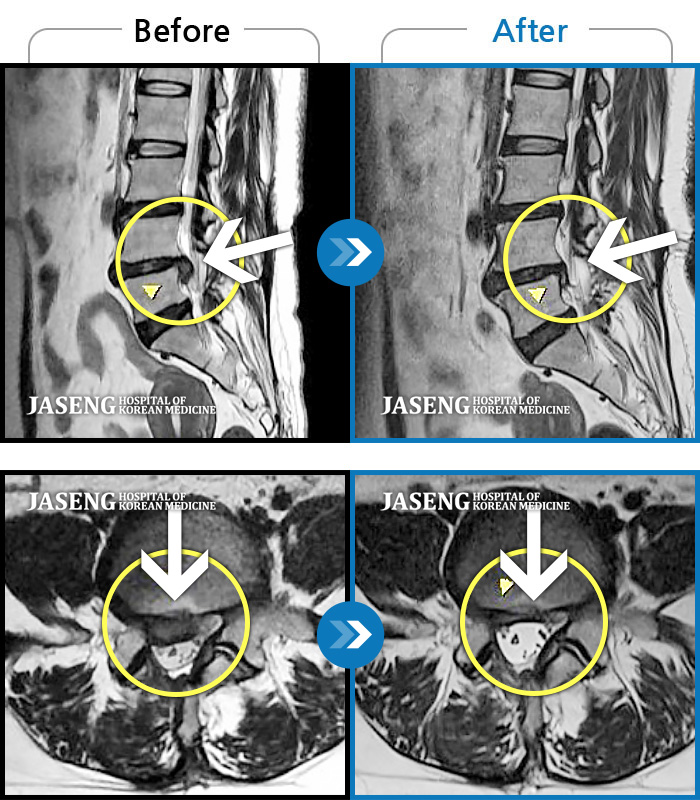

허리디스크

광주 · 장영우 원장

양측 허리부터 골반 묵직한 통증, 좌측 다리 외측까지 이어지는 당기는 통증으로 내원하셨습니다.

촬영시기

2503.04.01 ~ 2509.11.01

2025.09.22